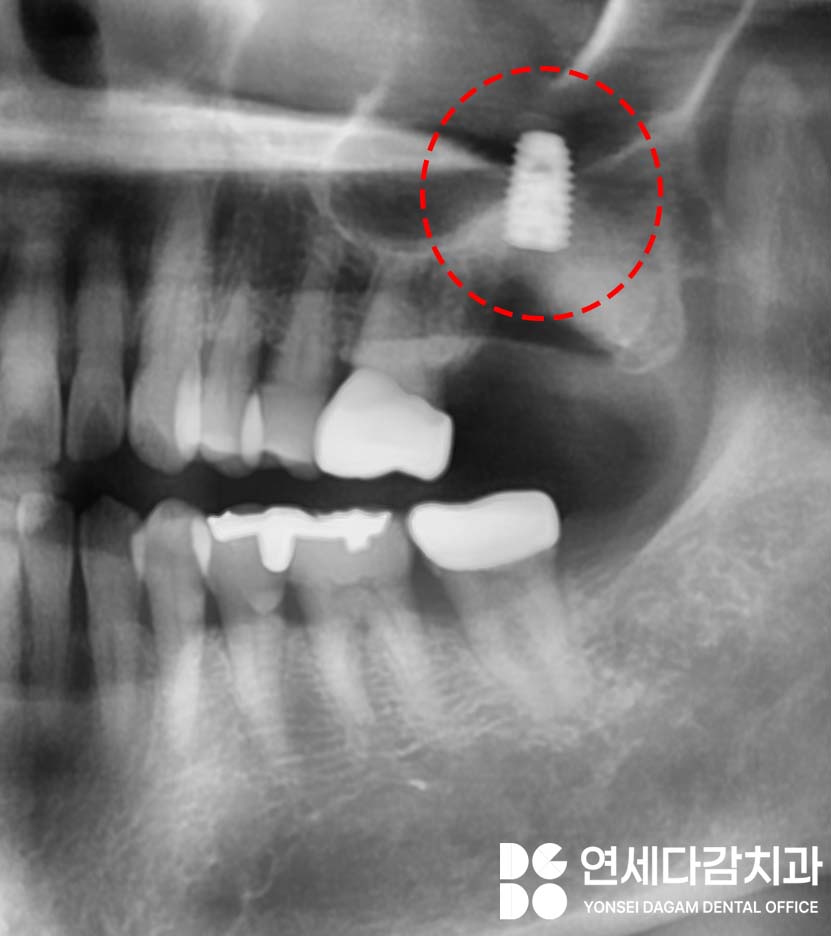

4개월 정도 충분한 치유가 이루어진 후,

임플란트 고정체를 식립했습니다.

기존에 많은 양이 소실된

치조골 높이를 회복시키는 데는

한계가 있기 때문에,

송파역 치과 에서는 안정된 부위를 찾아

다소 깊게 식립할 수밖에 없었습니다.

그러나 이것이 문제가 되는 것은 아닙니다.

이런 경우에는 환자의 구강 상태에 맞춘

맞춤형 임플란트 보철물을 제작하여

안정적으로 완성될 수 있습니다.